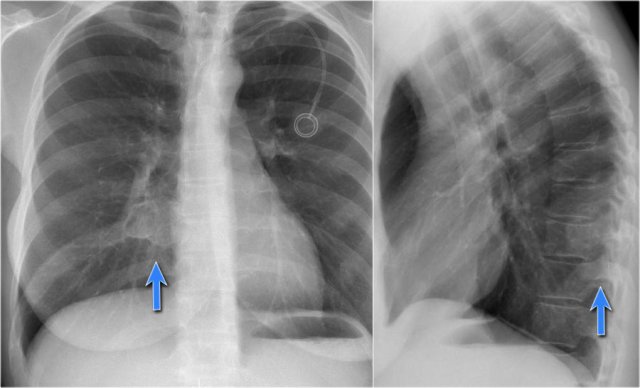

The contours of the left and right diaphragm should be visible.

The right diaphragm should be visible all the way to the anterior chest wall (red arrow).

Actually we see the interface between the air in the lungs and the soft tissue structures in the abdomen.

The left diaphragm can only be seen to a point where it borders the heart (blue arrow).

At that point the interface is lost, since the heart has the same density as the structures below the diaphragm.